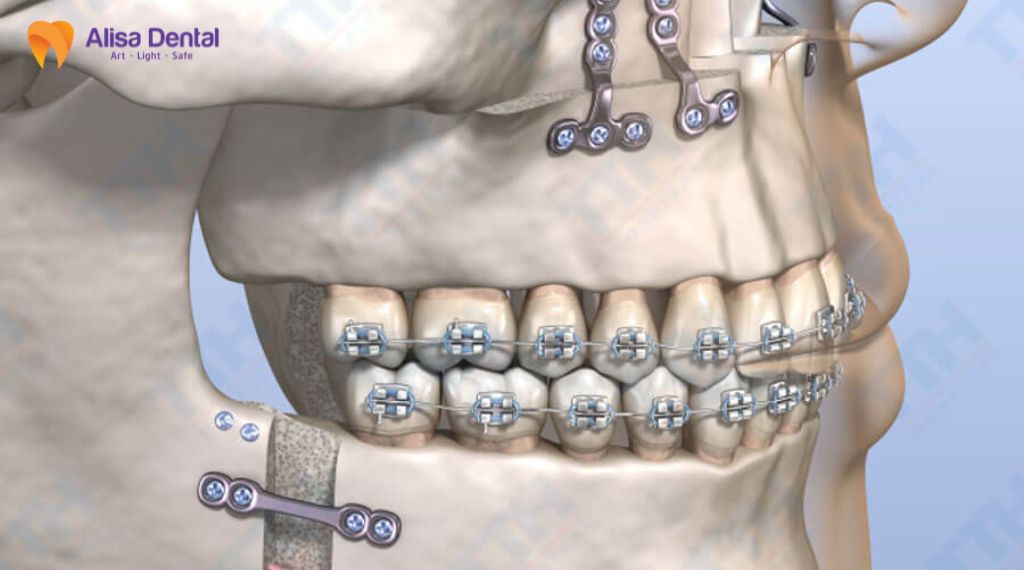

4 Cơ chế giải thích mối liên hệ giữa viêm nha chu và bệnh tim mạch

Để trả lời câu hỏi nha chu và bệnh tim mạch liên quan thế nào, các nhà khoa học đã đưa ra 4 cơ chế sinh học chủ chốt nhằm lý giải mối liên hệ phức tạp này. Những cơ chế này không chỉ tồn tại riêng lẻ mà còn có thể tương tác, bổ trợ lẫn nhau, qua đó cho thấy ảnh hưởng toàn thân của bệnh lý nha chu đối với hệ tim mạch

Mô hình viêm hệ thống (Systemic Inflammation)

Khi mô nha chu bị mầm bệnh tấn công, cơ thể sẽ phản ứng bằng cách giải phóng các cytokine viêm như CRP, IL-6, IL-1β và TNF-α vào hệ tuần hoàn. Các chất này khi lưu thông trong hệ tuần hoàn sẽ gây tổn thương lớp nội mạc mạch máu, tạo điều kiện thuận lợi cho việc hình thành mảng xơ vữa. Ngoài ra, tình trạng viêm mạn tính kéo dài có thể góp phần làm tăng nguy cơ bệnh tim mạch và suy tim thông qua cơ chế stress oxy hóa và tổn thương nội mạc mạch máu.

Mô hình nhiễm trùng trực tiếp (Direct Infection)

Vi khuẩn từ mảng bám răng, đặc biệt là vi khuẩn “khét tiếng” Porphyromonas gingivalis, có thể xâm nhập trực tiếp vào dòng máu thông qua các vết loét ở nướu khi ăn nhai hoặc đánh răng. Chúng đi xuyên qua lớp nội mạc, gây rối loạn chức năng mạch máu, stress oxy hóa và rối loạn chuyển hóa lipid. Một số nghiên cứu đã phát hiện ADN của vi khuẩn nha chu trong mảng xơ vữa động mạch, cho thấy mối liên hệ sinh học giữa viêm nha chu và bệnh tim mạch.

Mô hình phản ứng chéo – Giả phân tử (Molecular Mimicry)

Một cơ chế quan trọng liên kết viêm nha chu với bệnh tim mạch là hiện tượng molecular mimicry. Protein GroEL/HSP60 của vi khuẩn nha chu có cấu trúc tương đồng với protein HSP60 của tế bào nội mạc mạch máu người. Khi hệ miễn dịch tạo kháng thể chống lại vi khuẩn, các kháng thể này có thể nhận diện nhầm tế bào nội mạc, gây phản ứng viêm mạch máu và thúc đẩy quá trình hình thành xơ vữa động mạch.

Mô hình nhạy cảm phổ biến (Genetic Susceptibility)

Một số cá nhân mang kiểu hình bạch cầu đơn nhân nhạy cảm (MO+) mang tính di truyền. Khi tiếp xúc với vi khuẩn nha chu, cơ thể họ sẽ phản ứng viêm thái quá bằng cách tiết ra các chất gây viêm gấp 3 – 10 lần so với người bình thường. Chính sự nhạy cảm này khiến họ dễ dàng đồng thời mắc cả viêm nha chu nặng lẫn các bệnh lý xơ vữa động mạch và đột quỵ.